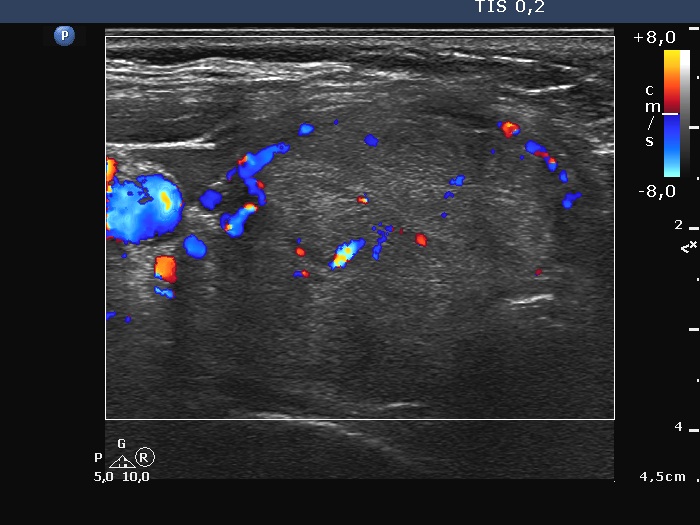

Right lobe, longitudinal scan

Right lobe, longitudinal scan, color Doppler mode. The lesion has perinodular flow.